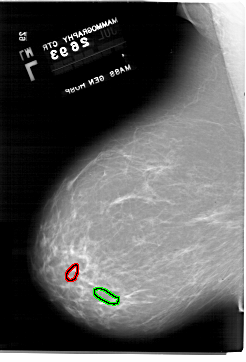

A_1918_1.LEFT_MLO

LEFT_MLO LINES 6871 PIXELS_PER_LINE 4666 BITS_PER_PIXEL 12 RESOLUTION 43.5 OVERLAY

FILE: A_1918_1.LEFT_MLO.OVERLAY

TOTAL_ABNORMALITIES 1

ABNORMALITY 1

LESION_TYPE CALCIFICATION TYPE PLEOMORPHIC DISTRIBUTION CLUSTERED

ASSESSMENT 4

SUBTLETY 2

PATHOLOGY BENIGN

TOTAL_OUTLINES 1

BOUNDARY

ABNORMALITY 2